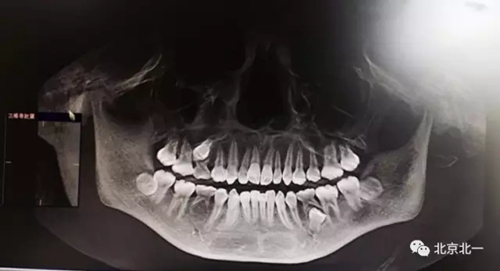

圖一:拔牙前影像片(CBCT)

正畸需要拔除埋伏牙拔除兩顆,采用微創(chuàng)舒適拔牙工具對埋伏牙進行有絲分裂,用埋伏牙攪碎機,攪碎牙齒后輕松取出。

總結(jié):埋伏牙如果直接硬撬可能會導致牙槽骨骨折。需要采用微動力系統(tǒng)將牙齒有絲分裂后拔除。